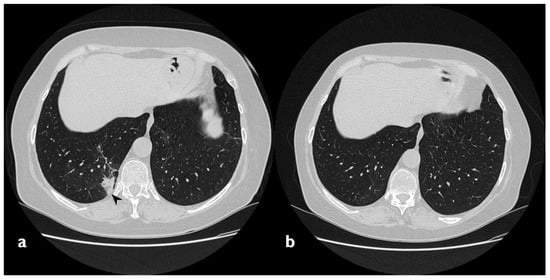

Figure 16. Fibrosing evolution. On the left (a): baseline HRCT. On the right (b): HRCT after 11 months of steroid therapy; new signs of fibrosis-sub-pleural basal reticulations and architectural distortion (arrowheads).

3.8. Evolution and Clinical Outcome

Two patients developed a fibrosing pattern despite the therapy (Figure 16). In more detail, in these two cases, we have observed multiple consolidations and ground-glass opacities at the beginning, with the partial resolution of these findings at follow-up HRCTs (the disappearance of ground-glass opacities and partial reduction of consolidations); however, they developed fibrotic changes like basal reticulations, bronchiectasis and fibrotic striae. Twenty-one patients (95.4%) received steroid therapy (oral corticosteroid, OCS) during the observation period of the study, and 17 of them had regression of radiological findings. Two patients had significant relapse after reducing/interrupting therapy (Table 11); both of them showed a typical consolidative picture at baseline. In one patient, relapse was characterized by the increase in multiple consolidations, particularly in the left lower lobe. This patient presented dry cough, dyspnea, crackles and inspiratory squawks, particularly in the left lower lobe. SpO2 level was 98%. In the other patient, the relapse was characterized by the appearance of multiple consolidations with air bronchogram. This patient presented exertional dyspnea, productive cough and important asthenia. SpO2 level was 98%. One patient refused steroid therapy and was followed up without any immunosuppressive therapy; for this patient, we did not observe any significant deterioration of functional data and radiological features.